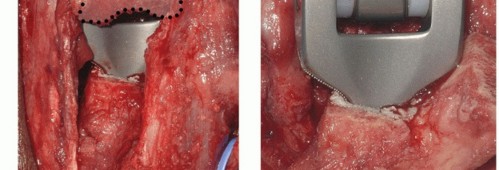

TECH FIG 5 • A. The prepared bony surfaces, with the fracture fragments removed, and just before implantation. B. The linked Coonrad-Morrey replacement is cemented and linked in situ. C. If in terminal extension there is abutment of the tip of the olecranon on the implant, the surgeon resects the olecranon tip (OT) but should not approach the triceps insertion footprint.